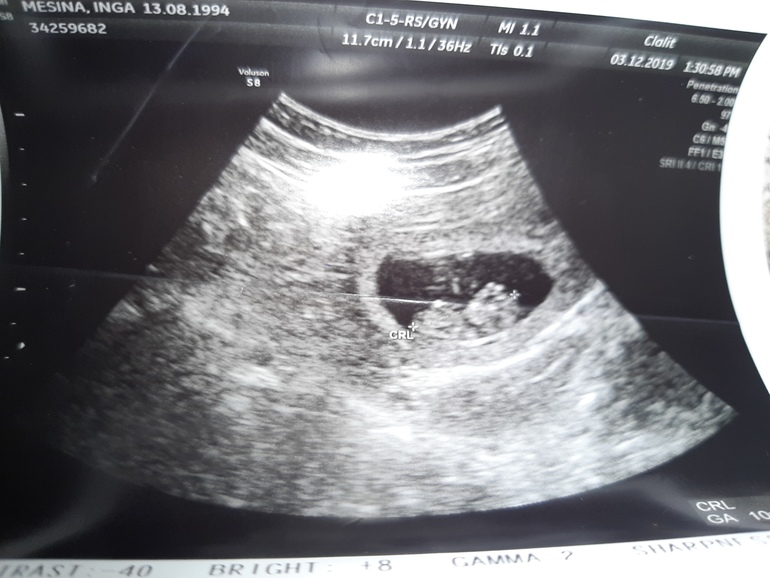

Разволновалась я что резко токсикоз прошел и грудь перестала болеть, побежала к врачу. Все хорошо у нас, растем, руки и ноги уже видны, сердце бьется))) 33 миллиметра) соответствует сроку. Счастье!